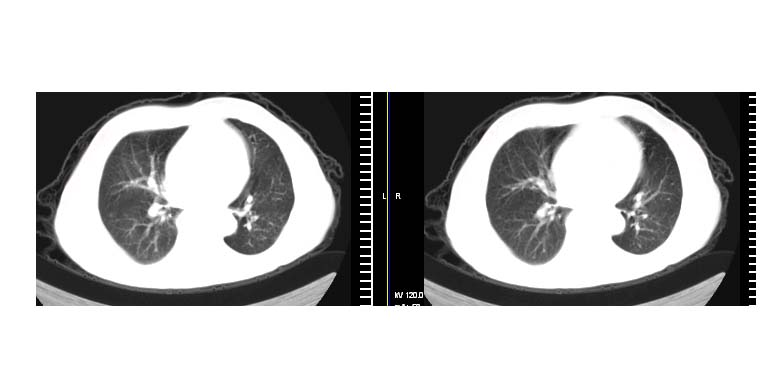

标题: CT11087:男性,82.咳嗽一周.抗炎治疗4-5天效果不明 [打印本页]

标题: CT11087:男性,82.咳嗽一周.抗炎治疗4-5天效果不明

左上肺实质性肿块,浅分叶 毛糙 胸膜凹陷征 纵隔淋巴结肿大——支持:左肺上叶周围型肺癌!

左上肺软组织肿块,有分叶,短毛刺,气管旁间隙见有肿大淋巴结,考虑左上周围型肺癌伴纵隔淋巴结转移。

考虑左上肺周围性肺癌(实性病灶有分叶,毛刺)可能性大。